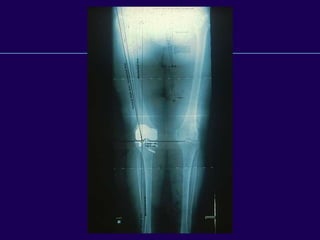

Radiographic Evaluation

—Standing full length – AP

—Standing AP

—Extension/Flexion laterals

—Tunnel view

—Sunrise view

Total Knee Arthroplasty

Weight Bearing X-rays

—Extent of joint space

narrowing

—Ligament stretch out

—Subluxation of femus on tibia